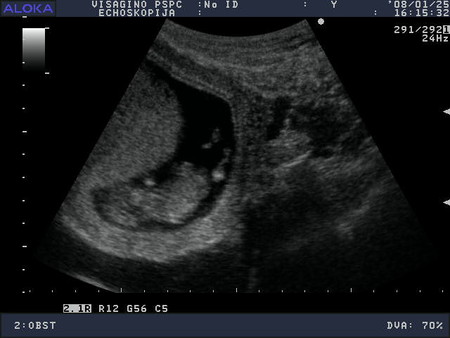

Vsem privet!Vhera bilaa na pervom uzi...vpehatlenij mnogo!Hto tam vitvoriaet rebenohek!!!Kuvirkaetsia i ruhki,nozki potiagivaet....prelest.Srok podtverdili 12 nedel i data rodov 08.08.2008

Nu a tam budet vidno.Skazali serdcebienie serjoznoe,poxoze tretij malhishka,nu da ne budem zagliadivat vpered.Ostavim eto na potom....v 20 nedelek pojdem posmotrim